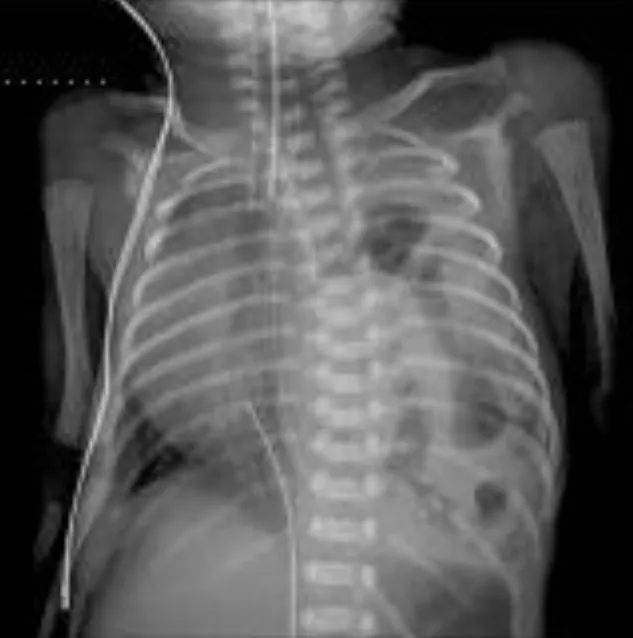

【114-2 醫學(五) 第46題】一名體重約 2.5 公斤的女嬰,出生時有呼吸窘迫、腹部凹陷的現象。X 光檢查發現在左側胸腔內充滿腸氣 (如圖)。下列敘述何者錯誤?

詳解

破題關鍵

這道題目的核心在於判斷先天性橫膈疝氣 (CDH) 的治療時機。圖片中新生兒X光片顯示左側胸腔有明顯的腸氣,這是診斷CDH的關鍵視覺線索。